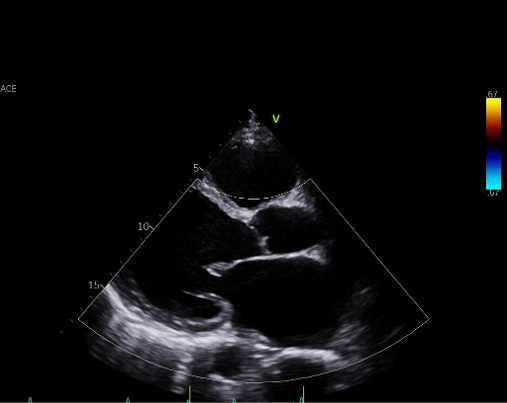

Chest X ray showed cardiomegaly. ECG showed atrial fibrillation rhythm with poor R progression. Echocardiography revealed markedly depressed left ventricular systolic function, with a left ventricular ejection fraction (LVEF) of 20.19%, accompanied by moderate mitral and tricuspid regurgitation.